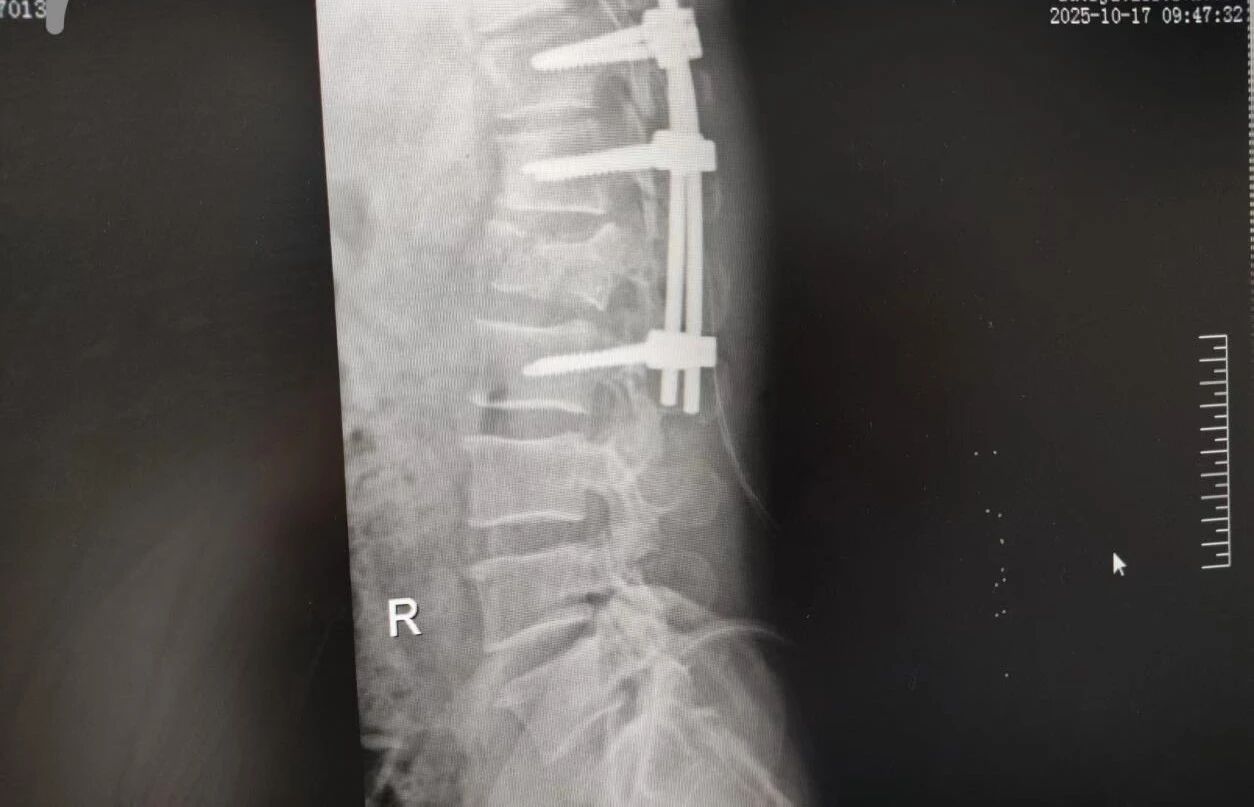

針對腰椎傷情,骨科竇志剛醫(yī)生團隊緊急開展腰 1 椎體爆裂性骨折切開復(fù)位內(nèi)固定術(shù) + 椎板切除減壓術(shù)。手術(shù)室、麻醉科無縫銜接開通綠色通道,手術(shù)團隊快速就位,術(shù)后患者下肢活動恢復(fù)自如。